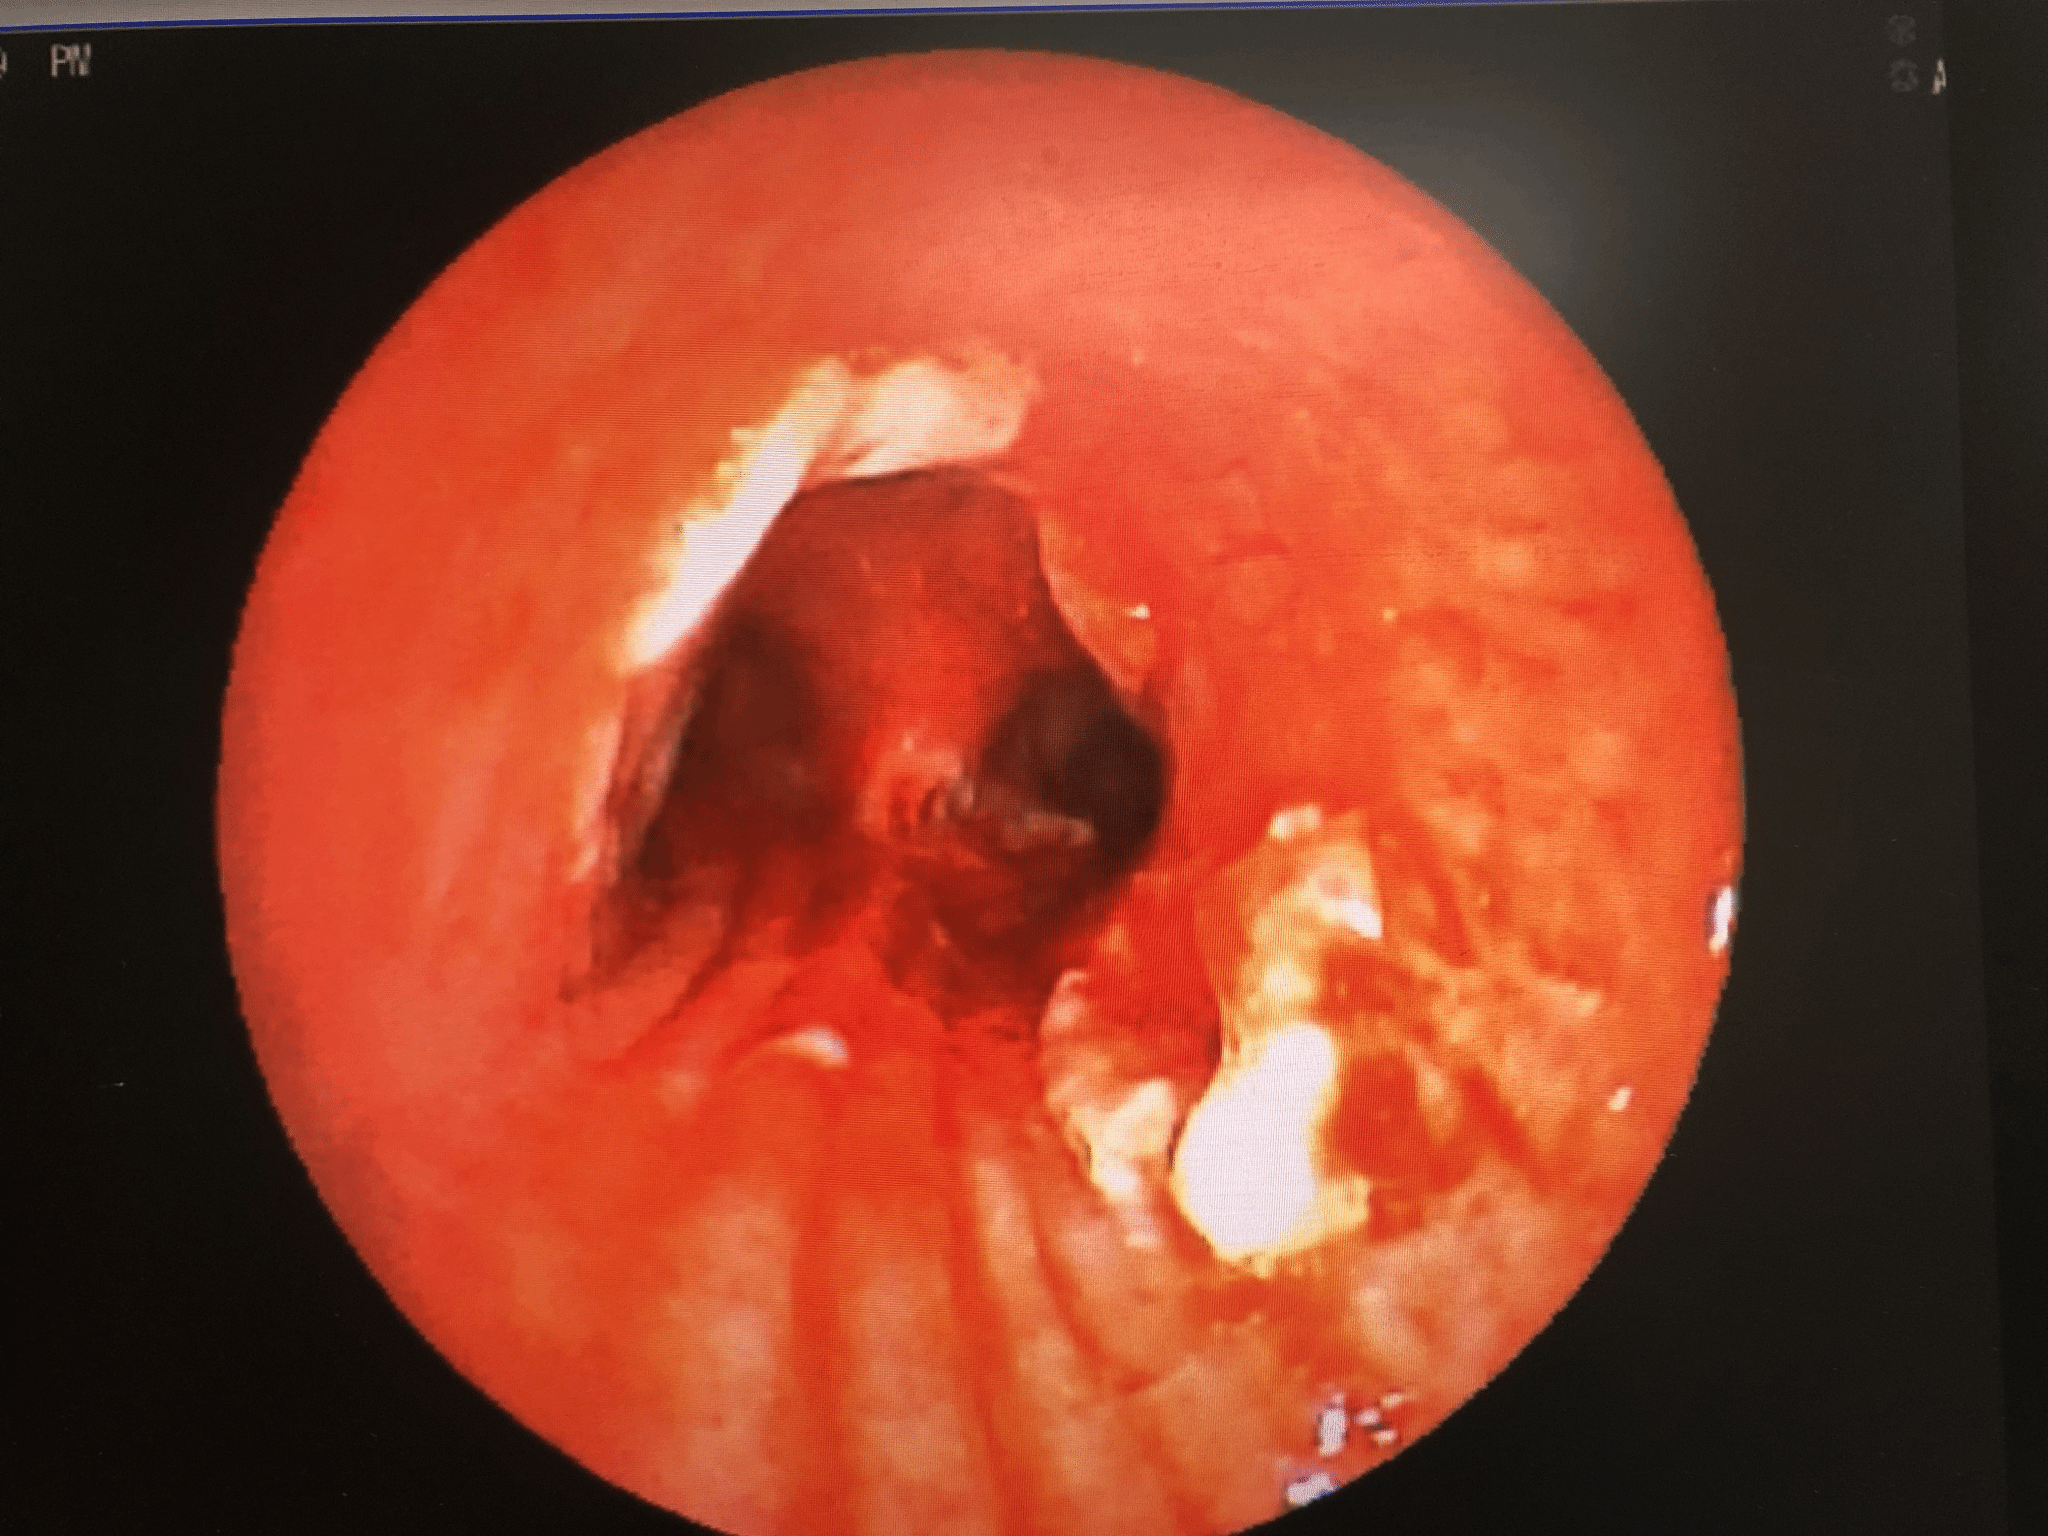

异物取出术

异物取出前 异物取出中

异物取出后 取出的异物